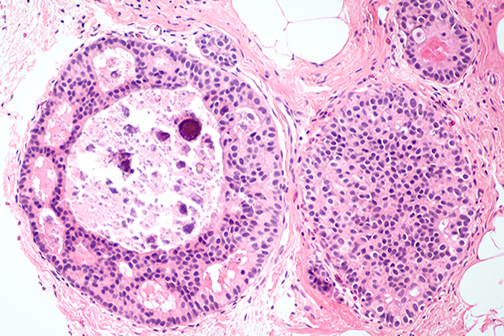

LSU Health Research Suggests A New Approach For Treatment-Resistant Breast Cancers

A collaborative study between LSU Health New Orleans School of Medicine, the University of Rochester and Cellestia Biotech AG, a biopharmaceutical company headquartered in Basel, Switzerland, provides compelling evidence that combining an investigational oral drug with standard-of-care medications reverts hormone resistance and increases Rx effectiveness in experimental models of estrogen-receptor positive (ER+) and triple-negative breast cancers (TNBC), respectively. More

LSU Health Research Finds New Drug Target for Triple-Negative Breast Cancer

Research led by Dr. Suresh Alahari, Professor of Biochemistry at LSU Health New Orleans’ Schools of Medicine and Graduate Studies, reports a combination of a novel small inhibitory molecule and an FDA-approved chemotherapy drug suppresses the growth of triple-negative breast cancer cells synergistically. More

LSU Health Research Suggests Novel Combination Therapy for Triple-Negative Breast Cancer

Research led by Suresh Alahari, PhD, Professor of Biochemistry at LSU Health New Orleans schools of Medicine and Graduate Studies, suggests a combination of drugs already approved by the FDA for other cancers may be effective in treating chemo-resistant triple-negative breast cancer. More